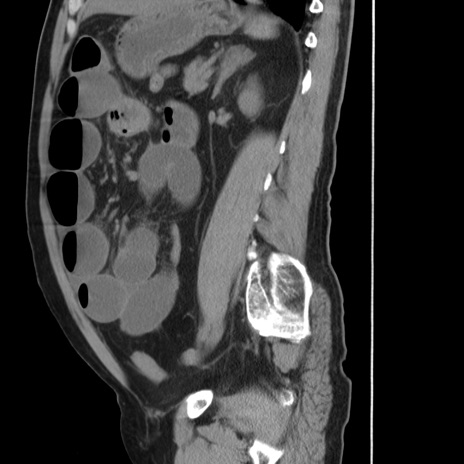

横断像

【症例】 60歳代男性

【主訴】 腹部膨満、嘔吐

【現病歴】5日前頃より倦怠感を認め食事量減少し4日前の朝嘔吐、食事摂取困難となった。 3日前近医受診し点滴施行され整腸剤などを処方された。 当日他院を受診し、腹部膨満著明、炎症反応の上昇(CRP10.8、WBC11200)あり、紹介受診となる。

【身体所見】 意識JCS1 受け答えがはっきりしないBP 111/57mHg、 P 67bpm、、BT35.2°C、SpO2 97%(RA)、 腹部:膨隆、打診で鼓音あり、全体的に圧痛有り、腸蠕動音(-)、反跳痛ははっきりせず。

【データ】WBC 11400、CRP 14.20